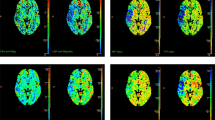

There were no stable radiomic features across acute and chronic ischemic hyperintensities in the first and second groups. Stable radiomic features across acute and chronic ischemic hyperintensities in the first group were 1.01% (1/99) in gray-level run-length matrix (GLRLM) and 2.22% (1/45) in neighboring gray tone difference matrix (NGTDM). Stable radiomic features across acute and chronic ischemic hyperintensities in the second group were 1.01% (1/99) in GLRLM. Stable radiomic features across acute ischemic hyperintensities in the first group were 2.17% (1/46) in the first order, 2.53% (5/198) in gray-level co-occurrence matrix (GLCM), 4.04% (4/99) in GLRLM, 2.22% (1/45) in local binary pattern (LBP), 1.71% (2/117) in gray-level size zone matrix (GLSZM), and 6.67% (3/45) in NGTDM. Stable radiomic features across chronic ischemic hyperintensities in the first group were 4.44% (2/45) in the second order, 2.02% (4/198) in GLCM, 6.06% (6/99) in GLRLM, 4.27% (5/117) in GLSZM, and 4.44% (2/45) in NGTDM. Stable radiomic features across acute ischemic hyperintensities in the second group were 2.17% (1/46) in the first order, 2.02% (4/198) in GLCM, 2.02% (2/99) in GLRLM, 2.22% (1/45) in LBP, 0.85% (1/117) in GLSZM, and 4.44% (2/45) in NGTDM. Stable radiomic features across chronic ischemic hyperintensities in the second group were 1.01% (1/99) in GLRLM, 2.22% (1/45) in LBP, and 2.22% (1/45) in NGTDM.

There were no stable radiomic features across acute and chronic ischemic hyperintensities using intersection ROIs in the first group. Stable radiomic features across acute and chronic ischemic hyperintensities in the second group were 1.01% (1/99) in GLRLM and 2.22% (1/45) in LBP. Stable radiomic features across acute ischemic hyperintensities in the first group were 4.35% (2/46) in the first order, 2.22% (1/45) in the second order, 1.01% (2/198) in GLCM, 4.04% (4/99) in GLRLM, 2.22% (1/45) in LBP, and 1.71% (2/117) in GLSZM. Stable radiomic features across chronic ischemic hyperintensities in the first group were 2.22% (1/45) in the second order, 2.53% (5/198) in GLCM, 6.06% (6/99) in GLRLM, 5.13% (6/117) in GLSZM, and 4.44% (2/45) in NGTDM. Stable radiomic features across acute ischemic hyperintensities in the second group were 6.52% (3/46) in the first order, 3.03% (6/198) in GLCM, 5.05% (5/99) in GLRLM, 2.22% (1/45) in LBP, 2.56% (3/117) in GLSZM, and 4.44% (2/45) in NGTDM. Stable radiomic features across chronic ischemic hyperintensities in the second group were 1.01% (1/99) in GLRLM and 4.44% (2/45) in LBP. All of the details mentioned above are shown in Figs. 1, 2 and 3.

Heat maps of radiomics features extracted from whole- and intersection ROI masks in the first and second groups. Features with CCC > 0.85 were regarded as stable. (a) Features from whole ROI masks in the first group. (b) Features from whole ROI masks in the second group. (c) Features from intersection ROI masks in the first group. (d) Features from intersection ROI masks in the second group. AIH acute ischemic hyperintensity, CIH chronic ischemic hyperintensity, CCC concordance correlation coefficients, ROI region-of-interest, EPI echo-planar imaging, ETL echo train length, TR repetition time.